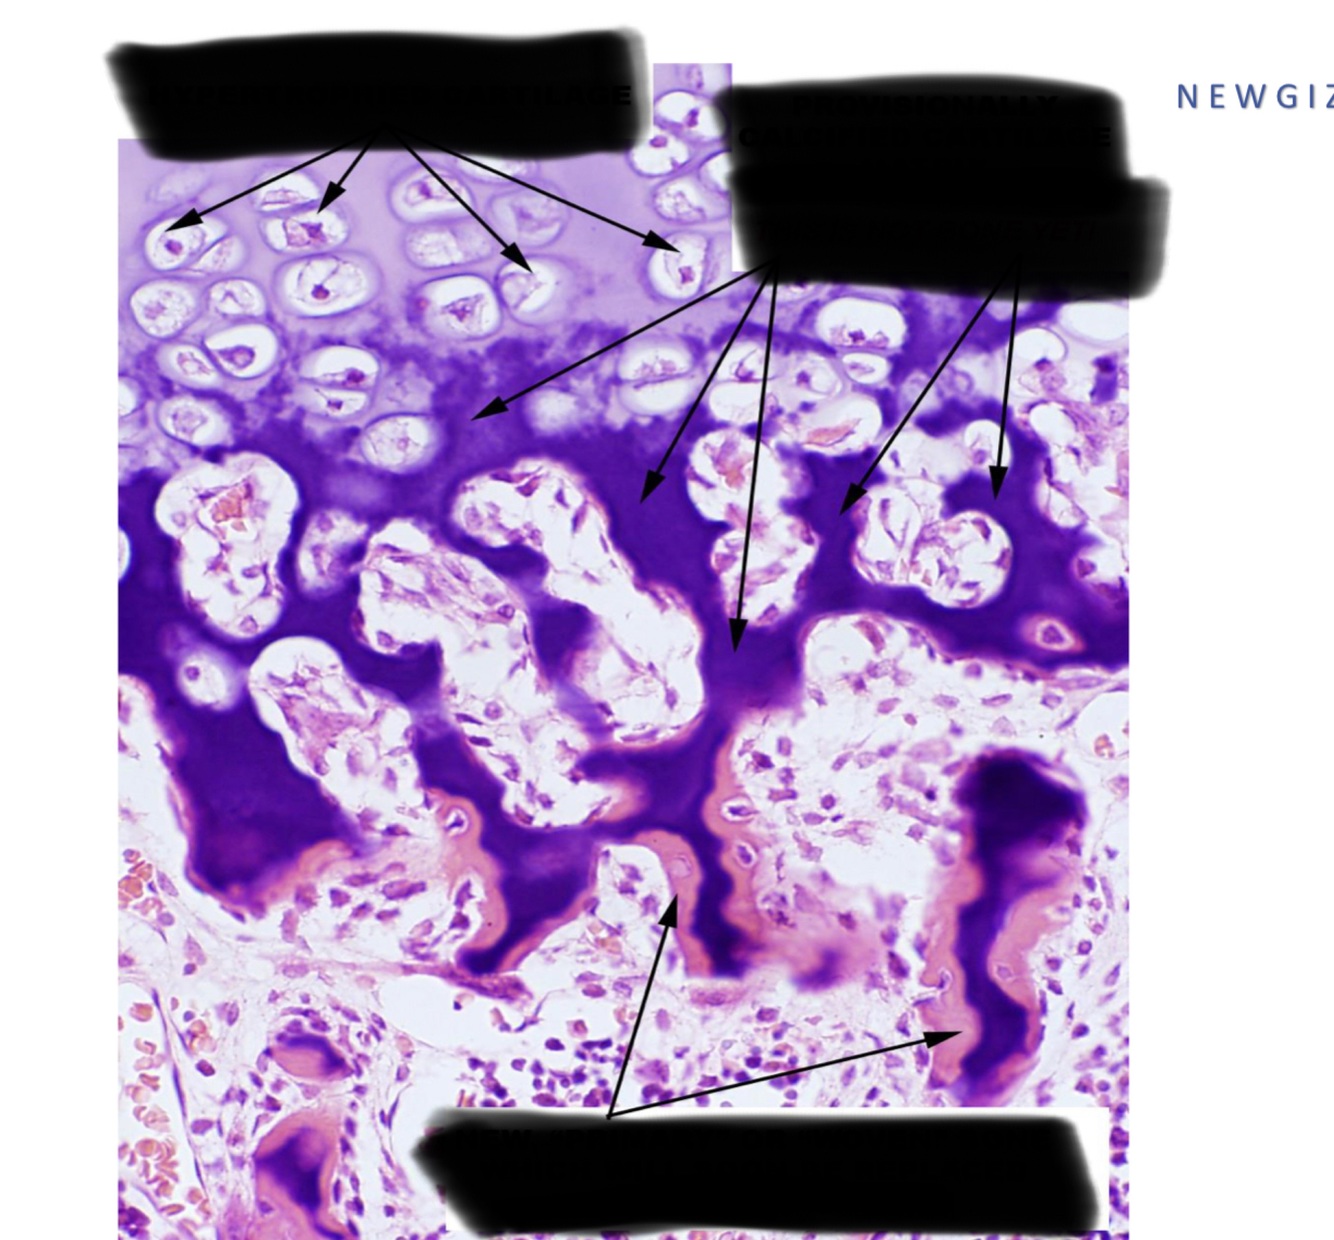

which is wooven and lamelar bone ?

Bone microscopy of Osteogenesis imperfect-a patient ; describe.